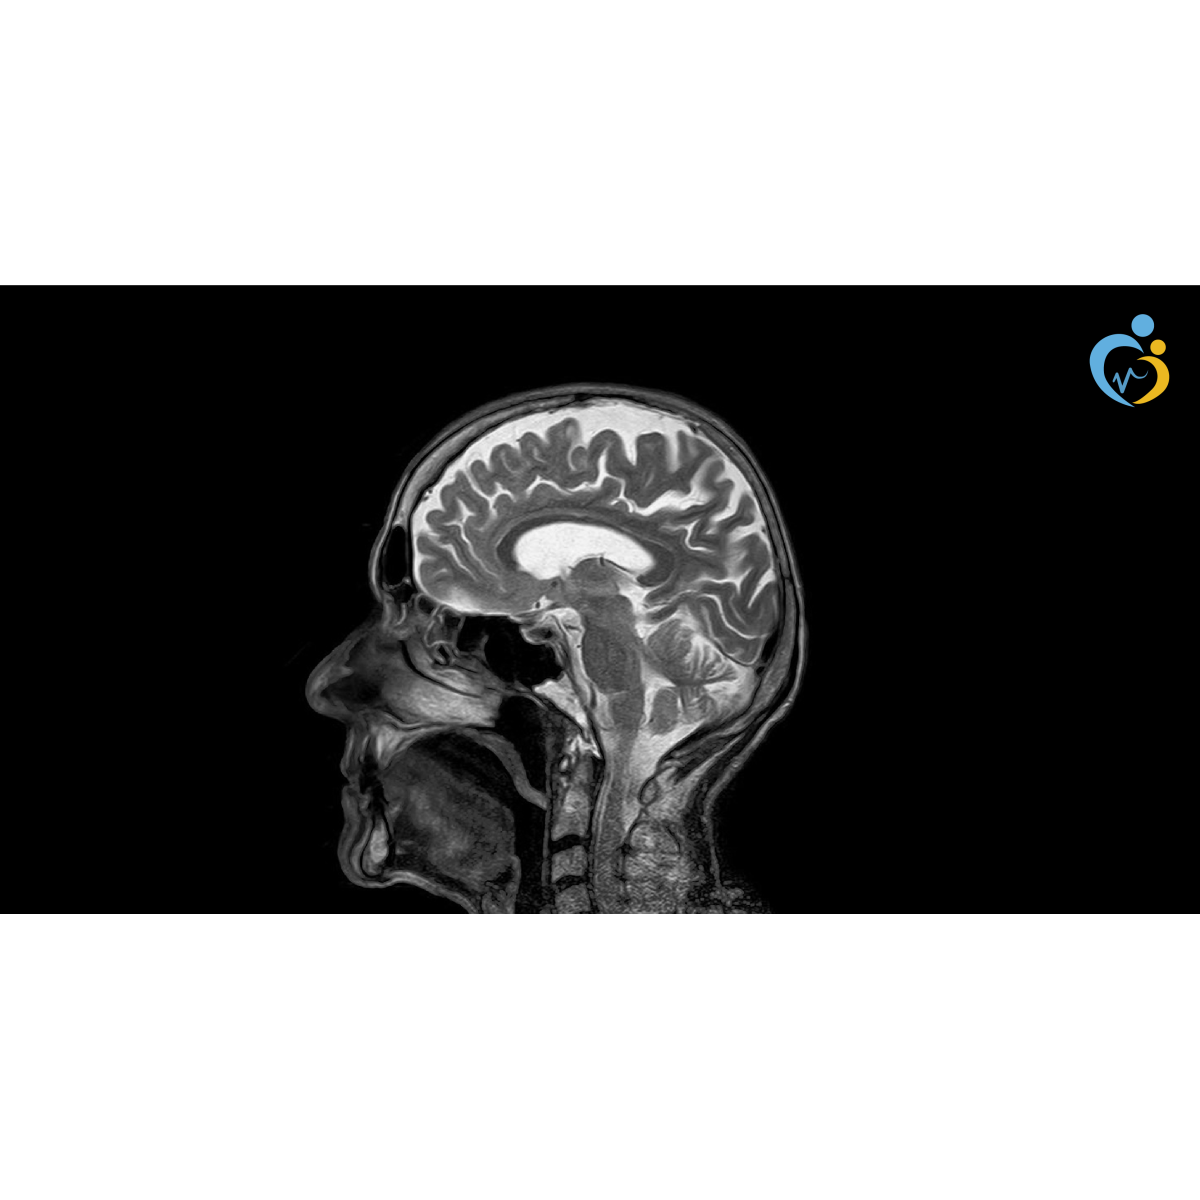

شرح فيزياء الرنين المغناطيسي الجزء الثالث موقع الأشعة التعليمي